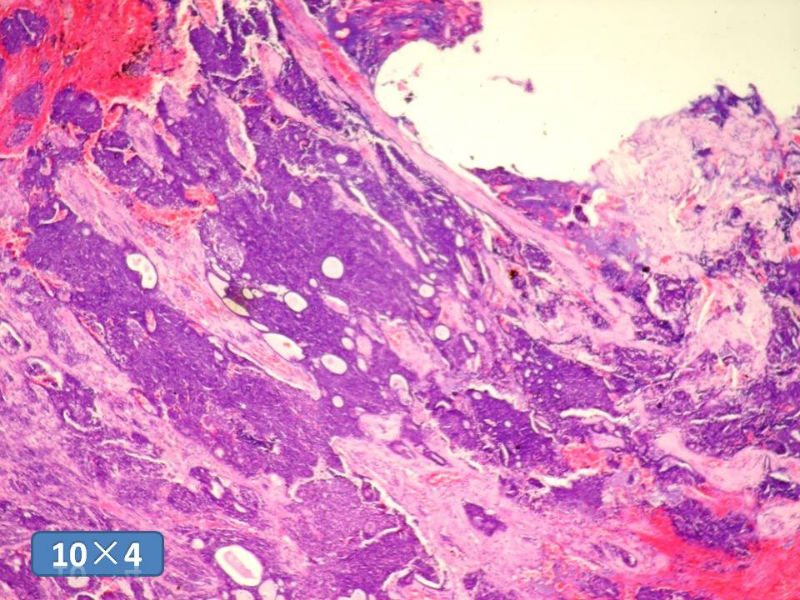

男性,49岁,间断左鼻腔出血3个月。

标签:是嗅母么?

有上皮和间叶2种结构,畸胎性癌肉瘤是要考虑一下的吧!

嗅神经母细胞瘤

支持嗅神经母细胞瘤(伴有腺体分化)

感觉要排除畸胎癌肉瘤。

间质为恶性梭形细胞成分,其间感觉是腺体,两种成分密切相关....

免疫组化S-100的阳性区域方式...嗅母可能性大。

腺肌上皮癌

1)嗅神经母细胞瘤?

2)腺肌上皮癌?

3)肌上皮癌?

4)神经内分泌癌?

5)腺样囊性癌?